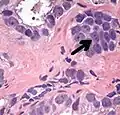

Intraductal carcinoma

Intraductal carcinoma of the prostate gland (IDCP), which is now categorised as a distinct entity by WHO 2016, includes two biologically distinct diseases. IDCP associated with invasive carcinoma (IDCP-inv) generally represents a growth pattern of invasive prostatic adenocarcinoma while the rarely encountered pure IDCP is a precursor of prostate cancer.[20] The diagnostic criterion of nuclear size at least 6 times normal is ambiguous as size could refer to either nuclear area or diameter. If area, then this criterion could be re-defined as nuclear diameter at least three times normal as it is difficult to visually compare area of nuclei.[20] It is also unclear whether IDCP could also include tumors with ductal morphology.[20] There is no consensus whether pure IDCP in needle biopsies should be managed with re-biopsy or radical therapy. A pragmatic approach would be to recommend radical therapy only for extensive pure IDCP that is morphologically unequivocal for high-grade prostate cancer.[20] Active surveillance is not appropriate when low-grade invasive cancer is associated with IDCP, as such patients usually have unsampled high-grade prostatic adenocarcinoma.[20] It is generally recommended that IDCP component of IDCP-inv should be included in tumor extent but not grade.[20] However, there are good arguments in favor of grading IDCP associated with invasive cancer.[20] WHO 2016 recommends that IDCP should not be graded, but it is unclear whether this applies to both pure IDCP and IDCP-inv.[20]

Intraductal carcinoma of the prostate with an infiltrative growth pattern may be morphologically difficult to distinguish from invasive cancer. One focus shows comedonecrosis (arrow), morphologically suggesting Gleason pattern 5 invasive carcinoma (a haematoxylin and eosin, b CK5/6)[20]

Intraductal carcinoma of the prostate with very patchy basal cells identified by immunohistochemistry. At least some of the glands lacking basal cell immunoreactivity represent intraductal rather than invasive carcinoma (a haematoxylin and eosin, b CK 5/6)[20]